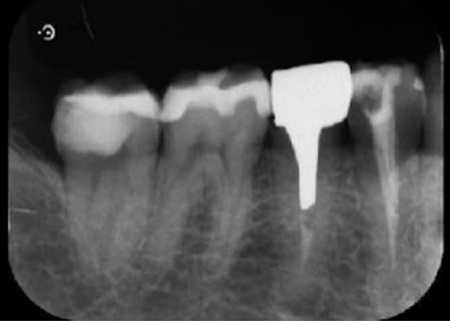

まず、右下奥歯(第2小臼歯)の周囲に唾液や細菌の侵入を防ぐためのゴム製のシート「ラバーダム」を装着し、マイクロスコープで細かく確認しながら感染部位を丁寧に除去します。

根管内が清潔になったら、再び細菌が入り込まないようしっかりと薬を詰めました。

レントゲン撮影で根尖病巣の治癒を確認後、最終的な被せ物を作製するため、歯の形を整えてから型取りを行います。

また、右下奥歯2本(第1大臼歯、第2大臼歯)に詰められていたコンポジットレジンを取り除き、併せて虫歯も丁寧に除去します。

その後、歯の形を整えて型取りを行いました。

後日、完成したE-MAXクラウンとプラチナインレーを装着し、噛み合わせや見た目に問題がないことを確認して、治療を終了しています。